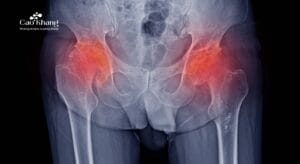

Thoái hóa khớp gối là quá trình sụn khớp và xương dưới sụn tại khớp gối bị bào mòn, nứt vỡ hoặc hư hại theo thời gian. Bệnh diễn tiến chậm nhưng không thể đảo ngược, là hệ quả tất yếu của quá trình lão hóa hoặc chịu các tác động tiêu cực kéo dài như chấn thương, vận động quá mức, béo phì…

Triệu chứng điển hình

Thoái hóa khớp gối biểu hiện qua các triệu chứng thường gặp như: